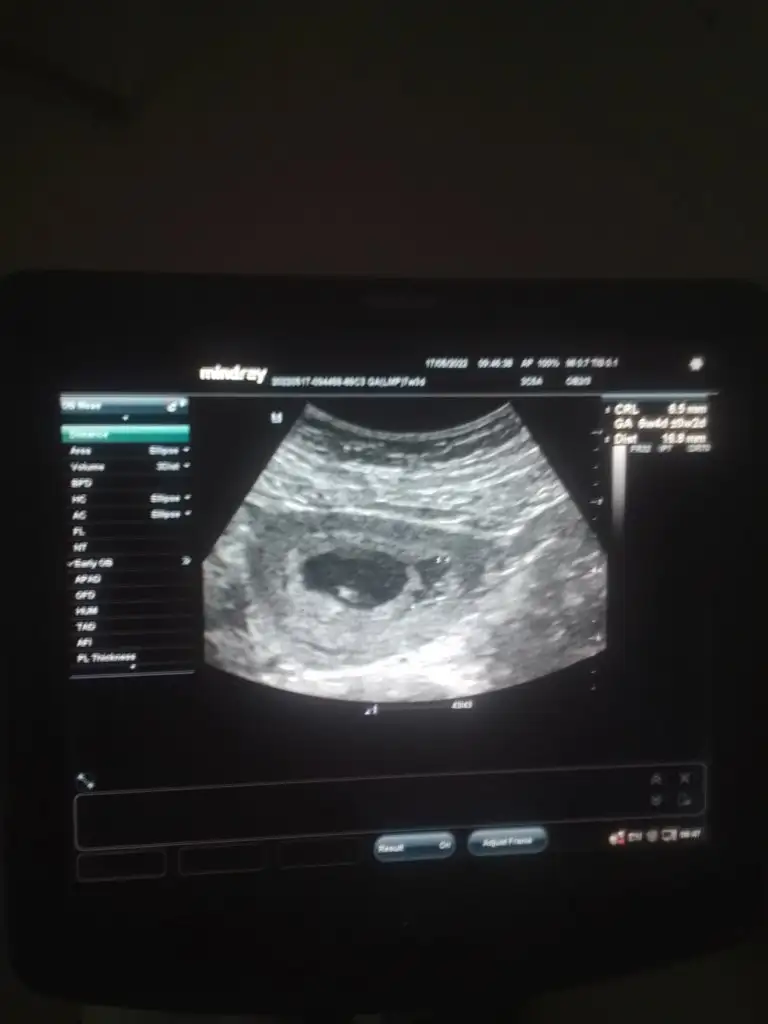

Bana bakarmisiniz rica etsem9 hafta 2 günlük karından bakildi